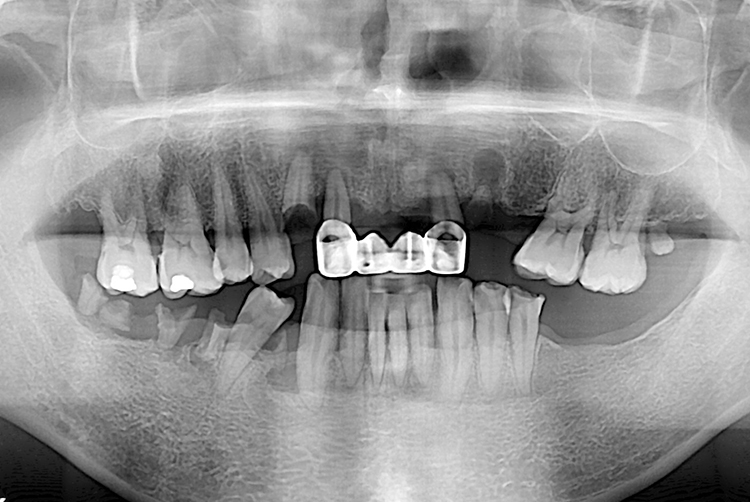

[임플란트] 임플란트

148b6c4b641a833921069b7094b20236.jpg

치료전 : 2016-03-23